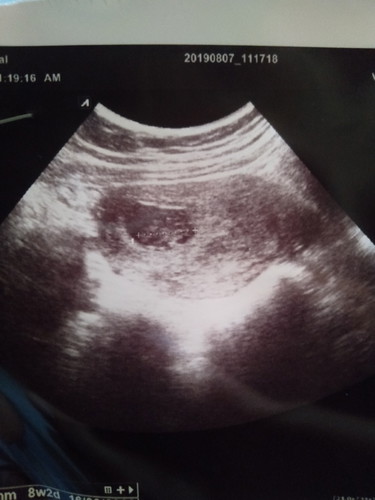

หมอบอกว่าอาจจะท้องลม หมอเลยนัดอีก2อาทิตย์ ในรูป8วีค 2วันค่ะ เจอตัวน้องแล้ว หัวใจก็เต้นปกติ แม่ดีใจมาก ตอนนี้10วีค1วันแล้วค่ะ?✌️✌️